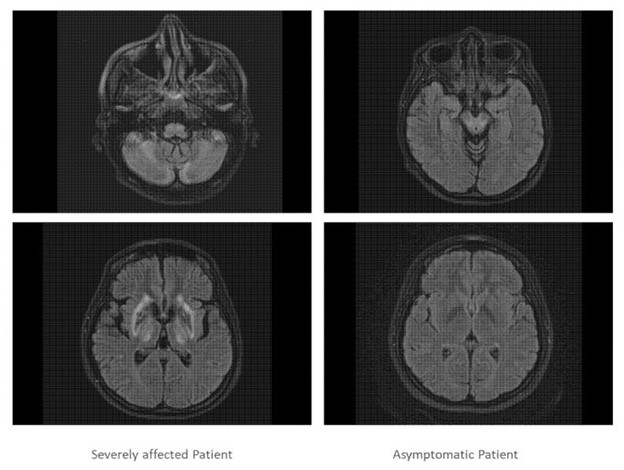

两姐妹都接受了进一步检查,证实姐妹 1 的大脑和肝脏严重受损,而姐妹 2 的脑成像正常,肝脏轻度受累(图 3)。

图 3:呈现了严重受影响的双胞胎(左侧)和无症状双胞胎(右侧)的两个头颅 MRI 扫描切片。严重受影响的双胞胎的 MRT 扫描显示皮质、基底节、小脑和脑桥核在疾病过程中严重参与,而无症状患者的 MRI 扫描则正常。 光学相干断层扫描 (OCT) 检查显示,两名患者双眼的视盘大小正常,视网膜神经纤维层 (RNFL) 几乎正常。在分段层中看不到随着 RNFL、GCIP 和 INL 直径减小的威尔逊病变化的具体模式。两名患者的OCT参数存在细微差异,但与正常对照组相比仍处于正常范围内。表 2)。 ;